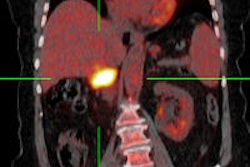

Furthermore, the session included a presentation dealing with PET/MRI, which can also help to reduce radiation doses in children, whilst at the same time enhancing additional diagnostic value. Used in pediatric tumoral disorders, this procedure not only displays metabolism within the organ, but also provides detailed anatomical information. Unlike PET/CT, an established procedure that has been around for longer, the new procedure generates far less radiation. However, availability remains a problem at the moment, with only four university sites to date in Germany equipped for PET/MRI systems.